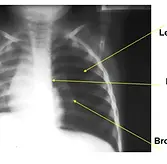

This eight year old boy complains of headache, lasting for last 3 months. No history of trauma. CNS exam including fundus was normal. Locallized tenderness noticed on the parietal side. No swelling. CT skull is enclosed

1. Radiological finding